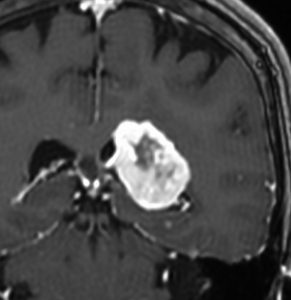

側脳室三角部髄膜腫 lateral ventricle (trigon) meningioma

50歳くらいの女性に偶然発見された三角部髄膜腫です。この部位はとても巨大にならないと症状が出ないので,しばらく様子を見ることにしました。

5年後です。増大傾向が止まりません。大きくなると手術リスクがすごく高くなるので,開頭手術で摘出することにしました。

右側は,手術翌日のMRIです。頭頂部の皮質経由で腫瘍は全摘出できています。専門的には,頭頂部経皮質到達法 parietal transcortical approach, high-parietal approachといいます。この患者さんは幸い頭頂葉症状は全く出ませんでした。でも巨大な三角部髄膜腫になると頭頂葉症候が手術後遺症として残ることがあります。でも慎重な手術をすれば日常生活に大きな支障となることはほとんどないでしょう。